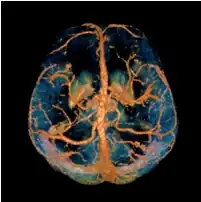

A volume rendered brain QSM acquired at 3 Tesla and reconstructed with morphology enabled dipole inversion (MEDI).

Quantitative susceptibility mapping (QSM) provides a novel contrast mechanism in magnetic resonance imaging (MRI) different from traditional susceptibility weighted imaging.[1][2][3][4][5]

The voxel intensity in QSM is linearly proportional to the underlying tissue apparent magnetic susceptibility, which is useful for chemical identification and quantification of specific biomarkers including iron, calcium, gadolinium, and super paramagnetic iron oxide (SPIO) nano-particles. QSM utilizes phase images, solves the magnetic field to susceptibility source inverse problem, and generates a three-dimensional susceptibility distribution. Due to its quantitative nature and sensitivity to certain kinds of material, potential QSM applications include standardized quantitative stratification of cerebral microbleeds and neurodegenerative disease, accurate gadolinium quantification in contrast enhanced MRI, and direct monitoring of targeted theranostic drug biodistribution in nanomedicine.